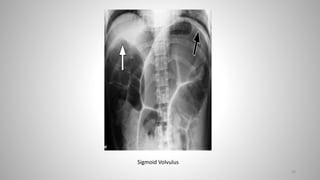

Volvulus

• Volvulus = Twisting of intestine upon itself

• Sigmoid volvulus is three to four times more common than cecal

Sigmoid Volvulus